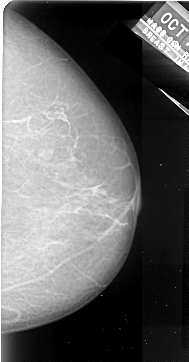

A_1006_1.RIGHT_MLO

RIGHT_MLO LINES 5401 PIXELS_PER_LINE 3226 BITS_PER_PIXEL 16 RESOLUTION 42 NON_OVERLAY